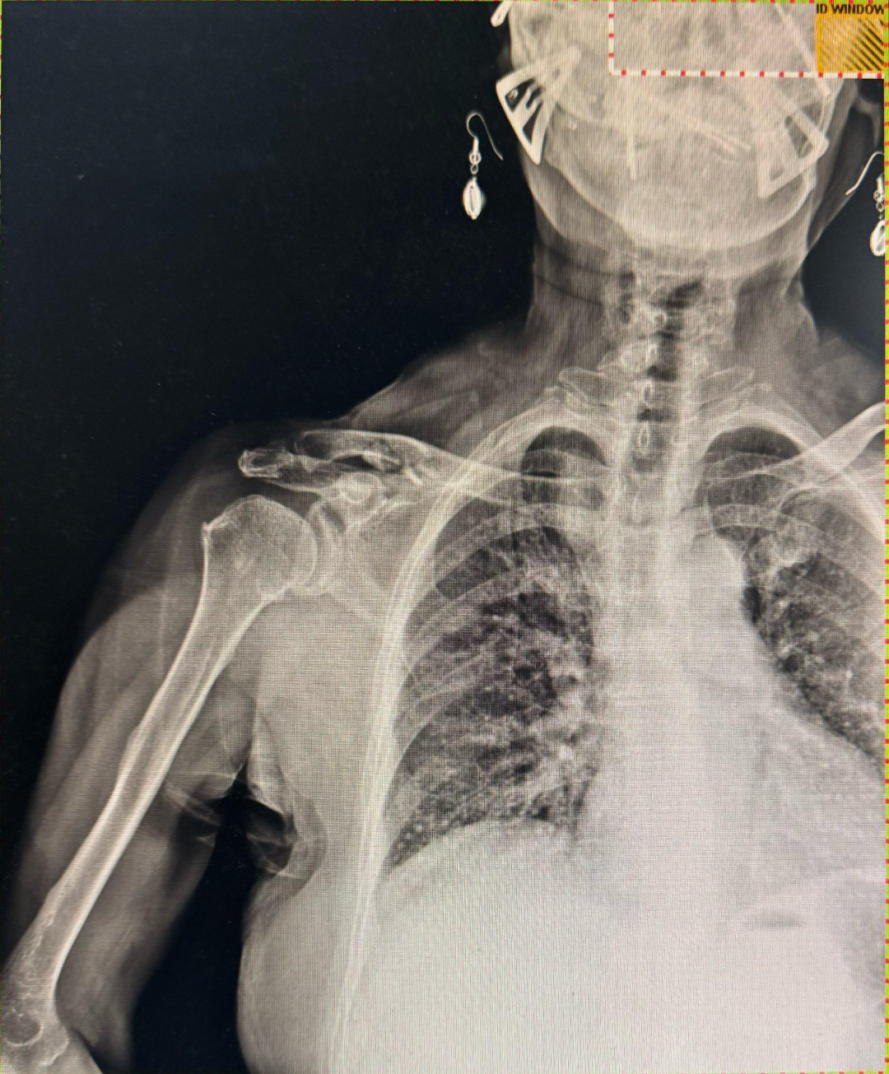

据悉,患者因不慎摔伤,导致右肩部出现剧烈疼痛,伴随活动受限。受伤后,患者第一时间前往附近医院就诊,经CT检查显示锁骨中段连续性中断,骨折断端重叠且呈粉碎性改变,接诊医生评估后建议住院进行手术治疗。患者家属考虑到手术存在创伤大、恢复周期长等问题,随即辗转来到西安市红会医院手法复位室,寻求保守的治疗方案。

复位后的影像学检查可见,骨折断端对位对线良好,重叠移位完全纠正,骨折形态恢复正常,无创治疗达到了理想的复位效果。整个治疗过程无需切口、无需麻醉,全程无创,患者在治疗中痛感轻微,极大减轻了身心负担。